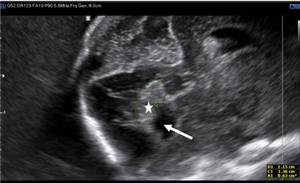

Ca lâm sàng: Thai ở sừng chột của tử cung một sừng